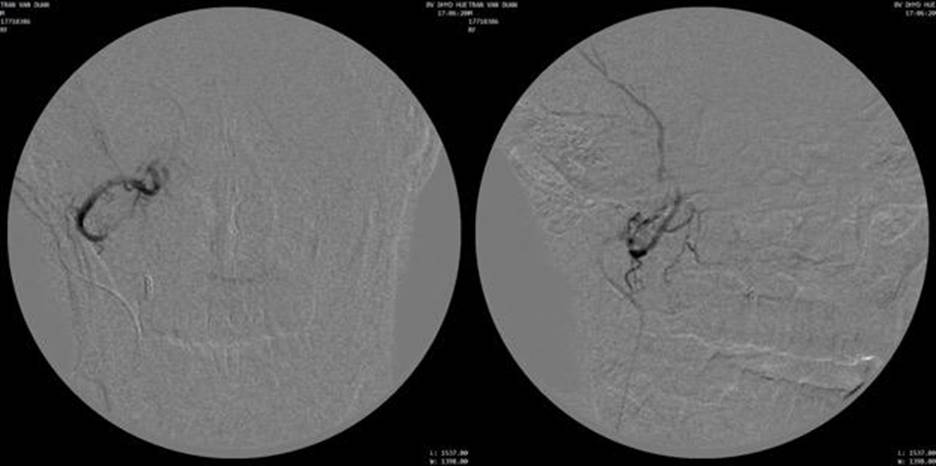

Chụp động mạch cảnh ngoài bên phải thấy khối u ở xoang hàm phải lan rộng, tăng sinh mạch, cấp máu từ nhánh động mạch mũi ngoài (lateral nasal artery) của động mạch mặt và động mạch huyệt răng sau trên (posterior superior aveolar artery) của động mạch hàm.

Chọn lọc nhánh nhánh động mạch mũi ngoài bằng vi ống thông (microcatheter Asahi 1.98F), chụp hình các mặt phẳng thẳng và nghiêng để xác định hình ảnh u ngấm thuốc (tumor staining) và nguồn cấp máu cho khối u. Nút mạch ngoại vi bằng hạt PVA contour 250-355μm, nút gốc động mạch mũi bằng 1 microcoil 2x70mm. Chụp kiểm tra thấy tắc hoàn toàn nhánh nuôi u.

Chọn lọc động mạch hàm, tiếp cận động mạch huyệt răng sau trên. Chụp chọn lọc thấy khối tăng sinh mạch với hình ảnh tumor network. Bơm tắc ngoại vi bằng hạt PVA 250-355μm. Nút tắc gốc bằng 01 detachable coil Interlock 5x150mm.

Chụp kiểm tra thấy tắc hoàn toàn mạch nuôi u, không thấy phần u ngấm thuốc.

Hình 3: Chụp động mạch mặt phải và chụp chọn lọc nhánh tận động mạch mũi ngoài, khối u ngấm thuốc mạnh, tăng sinh mạch trong u (hypervascularity)

Hình 4: Chụp kiểm tra sau nút mạch bằng hạt PVA và microcoil không còn thấy hình ảnh u ngấm thuốc

Hình 5: Chụp mạch chọn lọc nhánh nuôi u từ động mạch huyệt răng sau trên phải (từ động mạch hàm)

Hình 6: Chụp kiểm tra sau nút mạch không còn thấy u ngấm thuốc